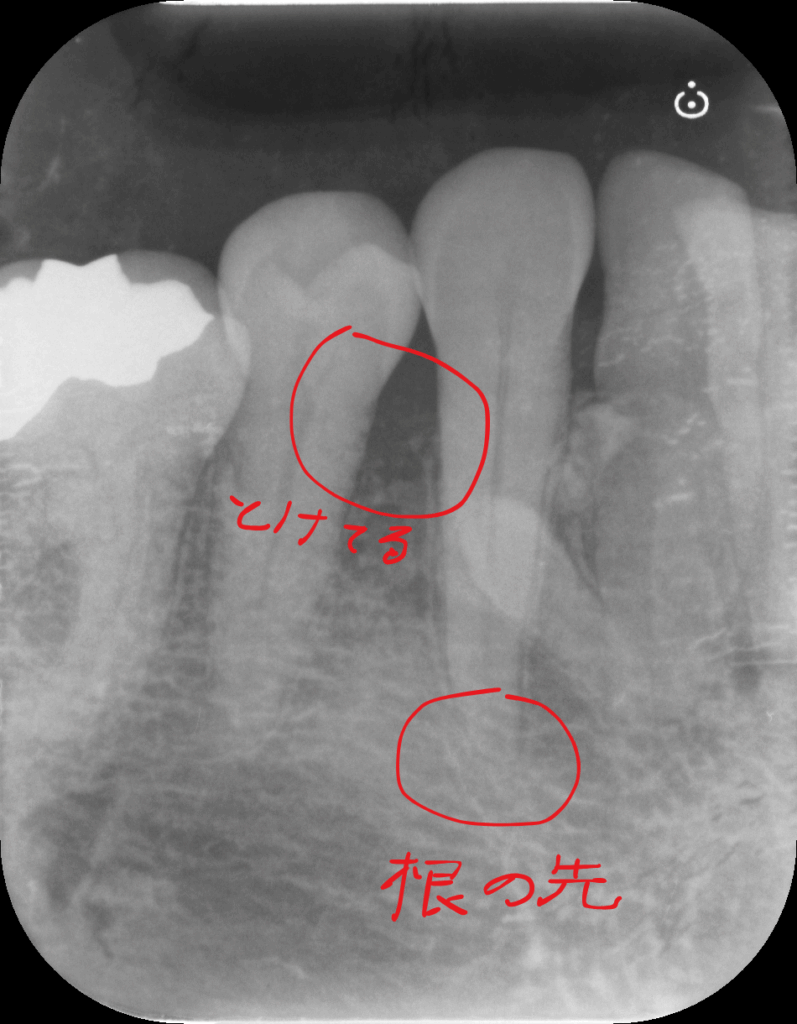

プローブがズボズボっと入っていきます。15mm以上これは歯根の先端まで達している状態です。

こんなときはレントゲンを撮るのが大切ですね。

レントゲンでは歯周病の所見も認めますが、レントゲンのみでは15mmもプローブが入るような写り方はしていません。

おそらく何か他にも原因があるのでしょう。(歯科関係者のみなさん過剰歯があるのは無視してください)